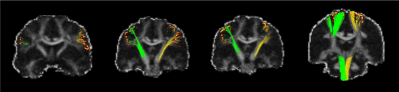

We selected the corticospinal tract (CST) as an example to test the algorithms. The CST has the features of large fanning and long range. The anatomy of CST is well known from the brainstem to the precentral gyrus [55]. The bundle masks are the voxels that ground truth fibers pass through after dilatation. In Fig. 7, we exhibit the details of the CST near area 4t (yellow boxes) and another regions (green boxes)(Brainetome regions [56]). Tractometer metrics with VC, OR, and OL for left and right CST are presented in Table. 4.

From the right column in Fig. 7, the BTD preserves better spatial fluency and is closer to the ground truth. The BTD tractography more fibers ending in precentral gyrus than iFOD2, SD_Stream, and UKF methods. While the UKF shows some twisted fibers and is unevenly distributed. The iFOD2 and SD_Stream show sparse and interrupted fibers. The BTD can track the large fanning fibers that ending nearby 4tl and 4hf in precentral gyrus. The iFOD2 and SD_Stream show fewer or no fibers in these regions. We can see that the VC and OL of iFOD2 and SD_Stream in Table. 4 are lower than BTD and UKF. In addition, the BTD has a lower OR compared with other three algorithms. The BTD seems to capture the complexity in regions where we expect fiber geometry (details are shown in Fig. 8). This is because the BTD reconstructs a bundle in a ‘cluster to cluster’ manner to reduce the ambiguous spatial correspondences between diffusion directions and fiber geometry. Therefore, the BTD preserves better spatial fluency and can better track the complex fibers than current peak-based tractography.